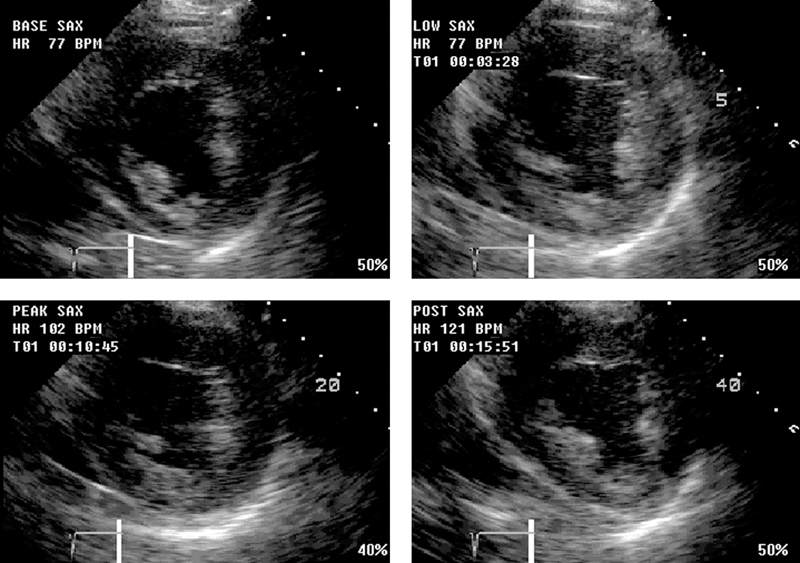

فحوصات تشخيصية لبعض امراض القلب والشرايين التاجية